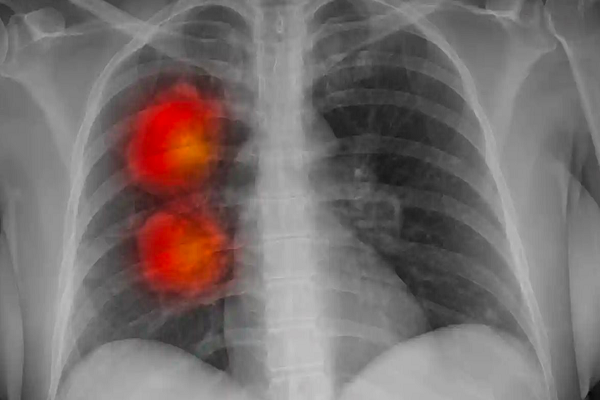

Công cụ trí tuệ nhân tạo có thể xác định chính xác bệnh ung thư

Các nhà khoa học đã xây dựng một mô hình trí tuệ nhân tạo (AI) có thể xác định chính xác bệnh ung thư để tăng tốc độ chẩn đoán bệnh và điều trị nhanh cho bệnh nhân.